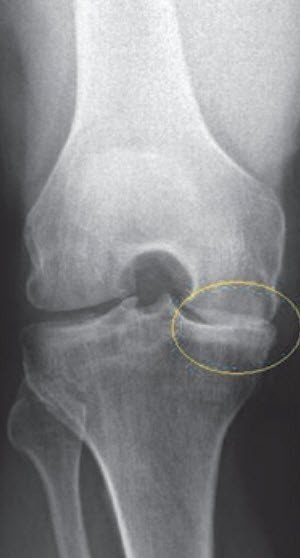

Die Arthrose, eine degenerative und meist altersbedingte Abnützung der Knorpeloberflächen, löst Entzündungen und damit Schmerzen im Knie aus. Allmählich wird die Knochenstruktur weiter geschädigt und die Beweglichkeit stark eingeschränkt. Eine Arthrose kann nicht heilen, sie schreitet in der Regel fort, bis das Kniegelenk komplett zerstört ist. Die Abnützung des Kniegelenks ist die häufigste Ursache für den Kniegelenkersatz.

Die Arthrose kann sich auch als Folge eines entzündlichen Rheumatismus oder Jahre nach Knieverletzungen und nach Meniskusoperationen entwickeln. Für die Patientinnen und Patienten sind das Ausmass der Knieschmerzen, das Hinken und die damit verbundene Behinderung ausschlaggebend, den Arzt aufzusuchen.

Ist von der Abnutzung nur der Kniescheibenteil oder der innere oder äussere Teil des Kniegelenks betroffen, kann ein teilweiser Gelenkersatz (Schlittenprothese / unikompartimentelle Kniearthroplastik) eingesetzt werden. Wichtige Voraussetzungen für die Indikation sind, dass sich die Arthrose hauptsächlich auf einen Abschnitt des Kniegelenks beschränkt und dass die Kniebänder noch funktionell sind.